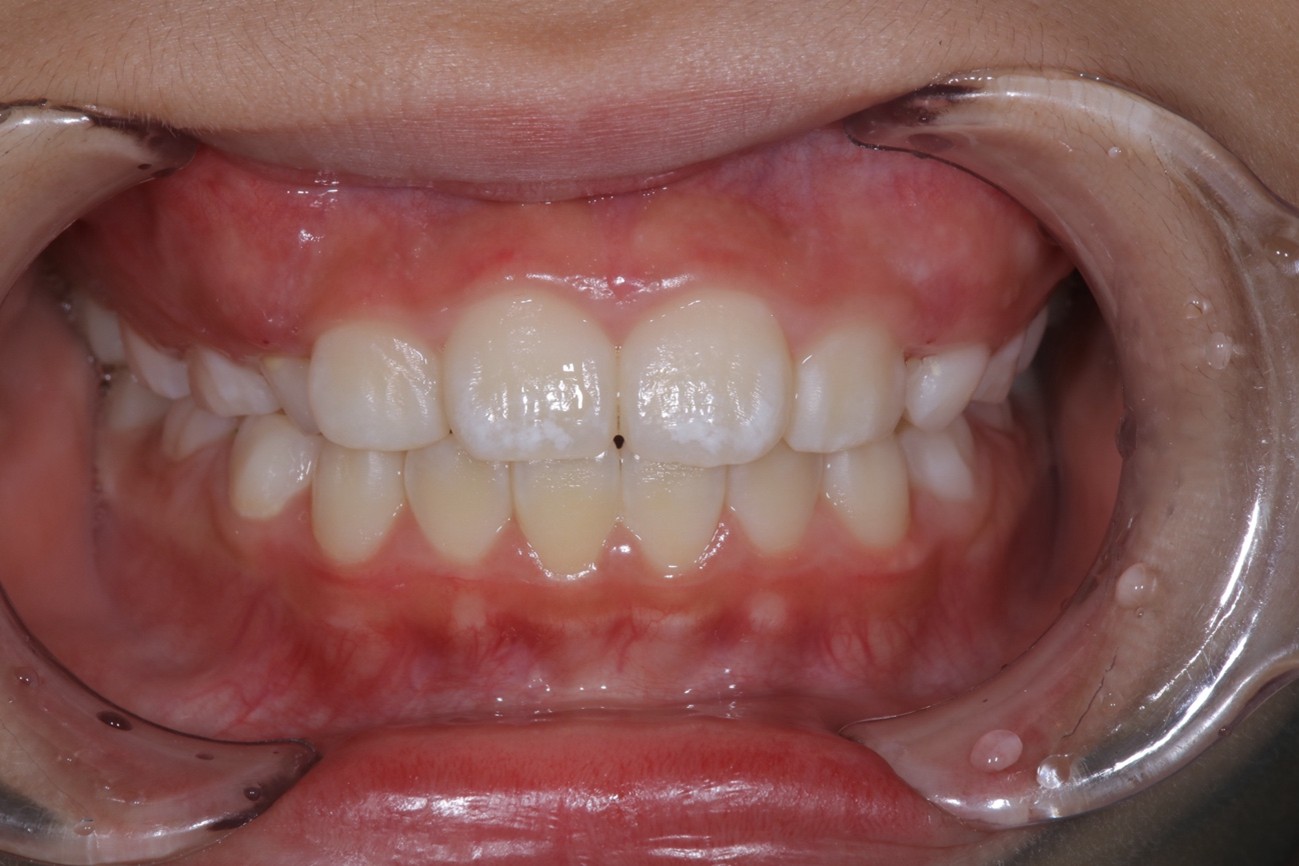

治療結果:上顎前歯の突出感の軽減による審美的な改善 口呼吸の改善

1年